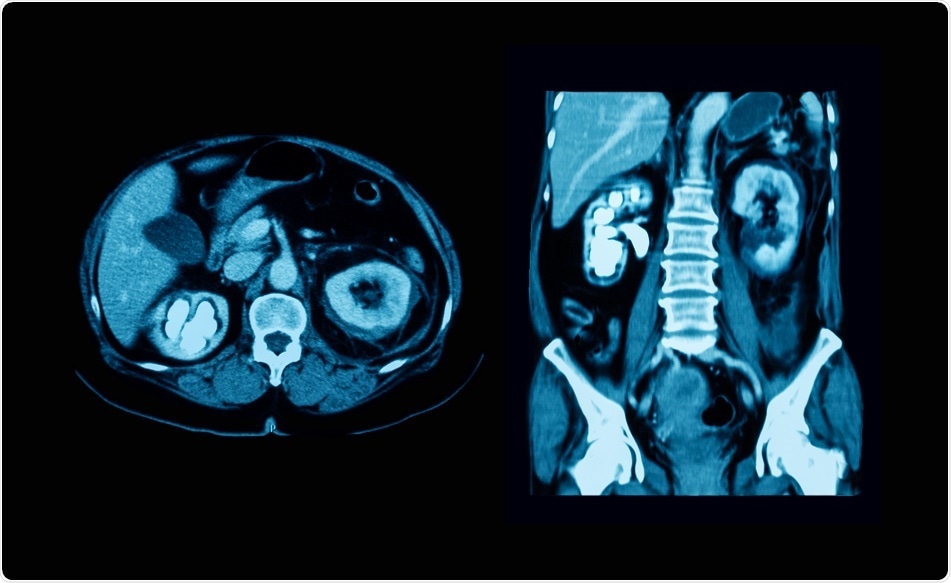

Credit: Suttha Burawonk/ Shutterstock.com

Although a computed tomography (CT) scan of the abdominopelvic region may be the imaging modality of choice for some, there are cases where ultrasound sonography of the urinary tract or radiographic images with or without contrast may be preferable. In addition to imaging tests, urinalysis and blood work may be ordered.

In contrast to the KUB radiograph, a CT scan is more expensive and exposes the patient to much higher doses of radiation. Moreover, smaller stones are difficult to see with CT scans and these scans may not identify some radiolucent calculi. To escape these disadvantages, the CT scan may be combined with KUB radiograph, based on many recommendations.

Nonetheless, the CT scan is an excellent imaging modality to help rule out more sinister pathologies, like abdominal aortic aneurysm, and, like the KUB radiograph, it can be used to determine the properties of the stone. This latter advantage is crucial for planning therapy.